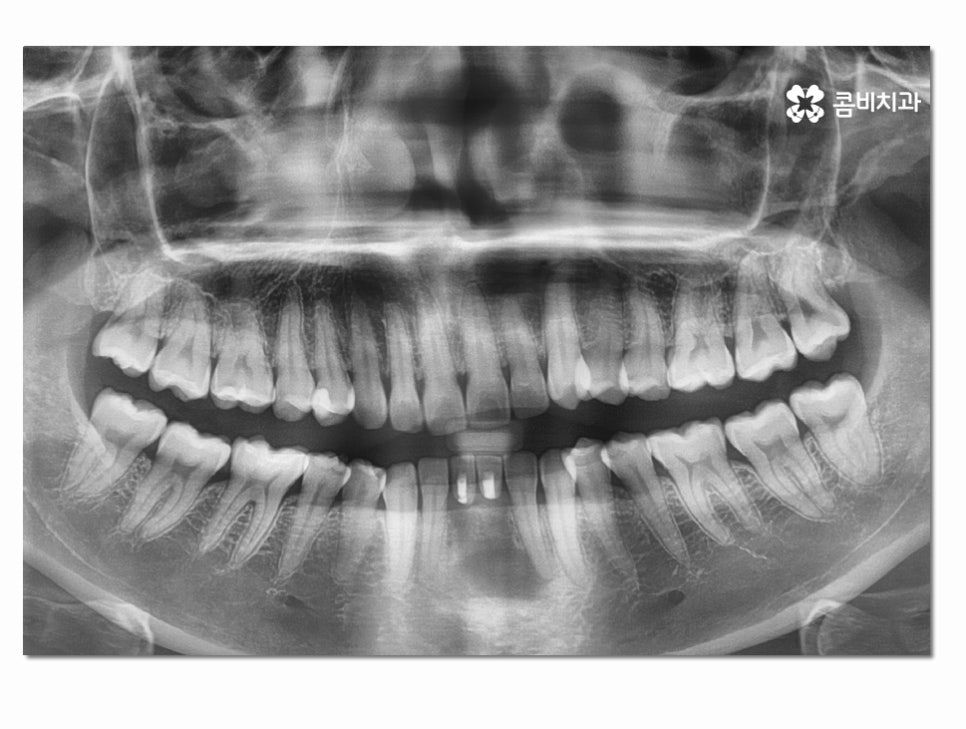

위 사진은 인공치근이 식립된 상태이고 인공치근이

잇몸뼈와 잘 유착이 되는지 확인하는 기간을

갖는 것이며 보철물을 결합하기 전에는 임시치아를 부착하고 있어요.

(좌 - 임플란트 식립 후 임시치아를 부착하고 안전하게 골 유착이 되도록 기다리는 과정, 보철물과 결합 준비 - 우)

인공치근이 튼튼하게 자리를 잡게 된 것이 확인이 되면

보철물을 주변 치아의 색과 모양과 비슷하게 제작하여

결합하는 과정을 거치고 아랫니 임플란트 치료 과정이 마무리될 수 있어요.